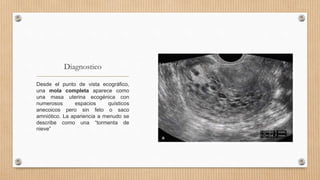

Desde el punto de vista ecográfico,

una mola completa aparece como

una masa uterina ecogénica con

numerosos espacios quísticos

anecoicos pero sin feto o saco

amniótico. La apariencia a menudo se

describe como una “tormenta de

nieve”